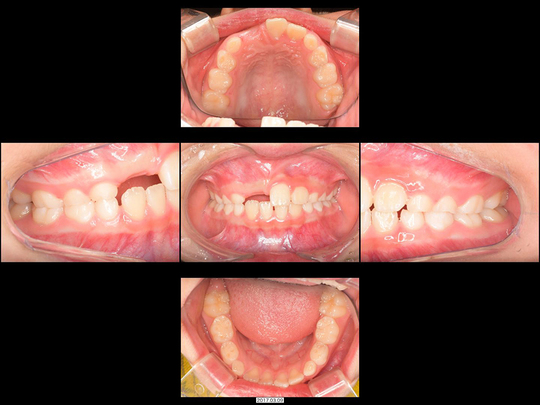

Yさん 9歳 男性

矯正前

矯正治療中

矯正後

治療の説明

前歯が生えてこないことをご不安に思われていたものの、「様子見しましょう」と言われ続けたとのことです。

CT検査の結果、埋伏している前歯に「過剰歯(かじょうし)」とよばれる余分な歯があり、本来の歯に引っかかっている状況でした。過剰歯を抜歯した後、事前に準備したお口の中に装着済みのワイヤー矯正装置で牽引を開始。奥歯の乳歯から永久歯の生え変わりのスペースもないので、併せてあごの骨も拡大しました。

治療の期間・回数

36か月、36回

​費用

618,000円

リスクや副作用:出血を伴う可能性があります。治療後に、痛みや腫れ、出血を引き起こす可能性があります。

装置に慣れるまでに1週間ほどかかる可能性があります。歯列を広げる過程で少し痛みを感じる可能性があります。装着時に多少しゃべりづらくなる可能性があります(2~3週間ほどで慣れます)。